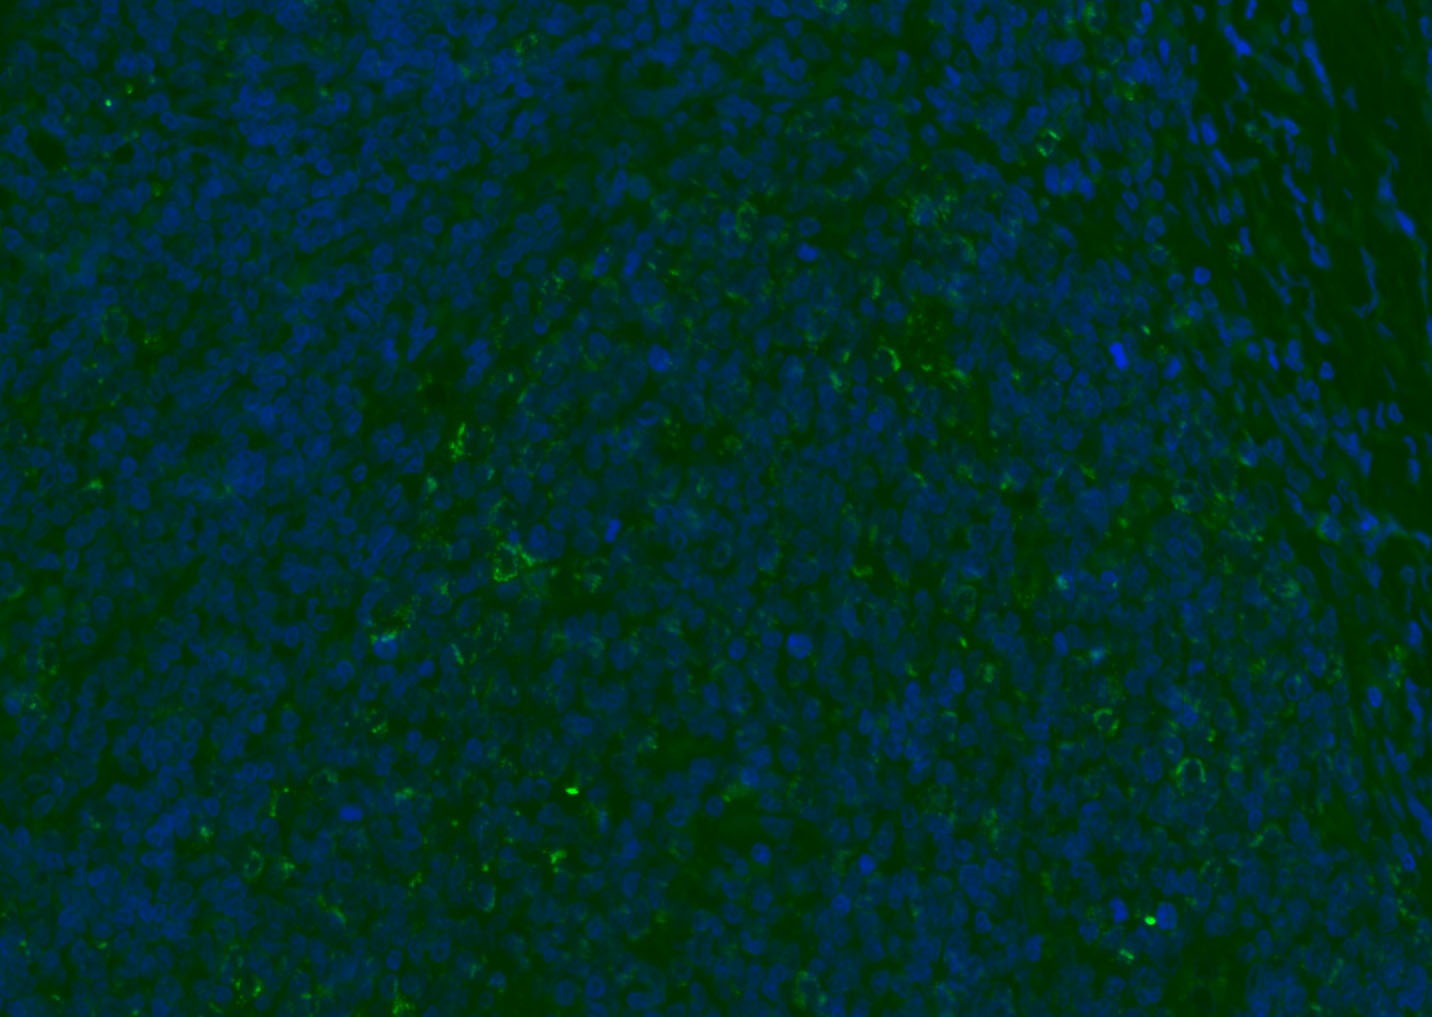

| Verified Activity | 1. Tissue/cell: human lung carcinoma;4% Paraformaldehyde-fixed and paraffin-embedded; Antigen retrieval: citrate buffer (0.01M, pH6.0), Boiling bathing for 15 min; Blocking buffer (normal goat serum) at 37°C for 20 min; Incubation: Anti-CD8 Polyclonal Antibody, Unconjugated (TMAB-00392) 1:200, overnight at 4°C; The secondary antibody was Goat Anti-Rabbit IgG, Cy3 conjugated used at 1:200 dilution for 40 minutes at 37°C. DAPI (5 μg/ml,blue) was used to stain the cell nucleus. 2. Paraformaldehyde-fixed, paraffin embedded (mouse lymphoid); Antigen retrieval by boiling in sodium citrate buffer (pH6.0) for 15 min; Blocking buffer (normal goat serum) at 37°C for 30 min; Antibody incubation with (CD8B) Polyclonal Antibody, Unconjugated (TMAB-00392) at 1:200 overnight at 4°C, followed by a conjugated Goat Anti-Rabbit IgG antibody for 90 minutes, and DAPI for nucleus staining. 3. Paraformaldehyde-fixed, paraffin embedded (rat spleen); Antigen retrieval by boiling in sodium citrate buffer (pH6.0) for 15 min; Blocking buffer (normal goat serum) at 37°C for 30 min; Antibody incubation with (CD8B) Polyclonal Antibody, Unconjugated (TMAB-00392) at 1:200 overnight at 4°C, followed by a conjugated Goat Anti-Rabbit IgG antibody for 90 minutes, and DAPI for nucleus staining. 4. Paraformaldehyde-fixed, paraffin embedded (mouse thymus); Antigen retrieval by boiling in sodium citrate buffer (pH6.0) for 15 min; Blocking buffer (normal goat serum) at 37°C for 30 min; Antibody incubation with (CD8B) Polyclonal Antibody, Unconjugated (TMAB-00392) at 1:200 overnight at 4°C, followed by a conjugated Goat Anti-Rabbit IgG antibody for 90 minutes, and DAPI for nucleus staining. 5. Paraformaldehyde-fixed, paraffin embedded (rat lymphoid); Antigen retrieval by boiling in sodium citrate buffer (pH6.0) for 15 min; Blocking buffer (normal goat serum) at 37°C for 30 min; Antibody incubation with (CD8B) Polyclonal Antibody, Unconjugated (TMAB-00392) at 1:200 overnight at 4°C, followed by a conjugated Goat Anti-Rabbit IgG antibody for 90 minutes, and DAPI for nucleus staining. 6. Paraformaldehyde-fixed, paraffin embedded (rat thymus); Antigen retrieval by boiling in sodium citrate buffer (pH6.0) for 15 min; Blocking buffer (normal goat serum) at 37°C for 30 min; Antibody incubation with (CD8B) Polyclonal Antibody, Unconjugated (TMAB-00392) at 1:200 overnight at 4°C, followed by a conjugated Goat Anti-Rabbit IgG antibody for 90 minutes, and DAPI for nucleus staining. 7. Paraformaldehyde-fixed, paraffin embedded (human tonsil); Antigen retrieval by boiling in sodium citrate buffer (pH6.0) for 15 min; Blocking buffer (normal goat serum) at 37°C for 30 min; Antibody incubation with (CD8B) Polyclonal Antibody, Unconjugated (TMAB-00392) at 1:200 overnight at 4°C, followed by a conjugated Goat Anti-Rabbit IgG antibody for 90 minutes, and DAPI for nucleus staining. 8. Paraformaldehyde-fixed, paraffin embedded (mouse lymphoid); Antigen retrieval by boiling in sodium citrate buffer (pH6.0) for 15 min; Blocking buffer (normal goat serum) at 37°C for 30 min; Antibody incubation with (CD8B) Polyclonal Antibody, Unconjugated (TMAB-00392) at 1:200 overnight at 4°C, followed by a conjugated Goat Anti-Rabbit IgG antibody for 90 minutes, and DAPI for nucleus staining. 9. Paraformaldehyde-fixed, paraffin embedded (rat thymus); Antigen retrieval by boiling in sodium citrate buffer (pH6.0) for 15 min; Blocking buffer (normal goat serum) at 37°C for 30 min; Antibody incubation with (CD8B) Polyclonal Antibody, Unconjugated (TMAB-00392) at 1:200 overnight at 4°C, followed by a conjugated Goat Anti-Rabbit IgG antibody for 90 minutes, and DAPI for nucleus staining. 10. Paraformaldehyde-fixed, paraffin embedded (human tonsil); Antigen retrieval by boiling in sodium citrate buffer (pH6.0) for 15 min; Blocking buffer (normal goat serum) at 37°C for 30 min; Antibody incubation with (CD8B) Polyclonal Antibody, Unconjugated (TMAB-00392) at 1:200 overnight at 4°C, followed by a conjugated Goat Anti-Rabbit IgG antibody for 90 minutes, and DAPI for nucleus staining. 11. Paraformaldehyde-fixed, paraffin embedded (mouse spleen); Antigen retrieval by boiling in sodium citrate buffer (pH6.0) for 15 min; Blocking buffer (normal goat serum) at 37°C for 30 min; Antibody incubation with (CD8B) Polyclonal Antibody, Unconjugated (TMAB-00392) at 1:200 overnight at 4°C, followed by a conjugated Goat Anti-Rabbit IgG antibody for 90 minutes, and DAPI for nucleus staining. 12. Paraformaldehyde-fixed, paraffin embedded (rat lymphoid); Antigen retrieval by boiling in sodium citrate buffer (pH6.0) for 15 min; Blocking buffer (normal goat serum) at 37°C for 30 min; Antibody incubation with (CD8B) Polyclonal Antibody, Unconjugated (TMAB-00392) at 1:200 overnight at 4°C, followed by a conjugated Goat Anti-Rabbit IgG antibody for 90 minutes, and DAPI for nucleus staining. 13. Paraformaldehyde-fixed, paraffin embedded (Rat lymphoid); Antigen retrieval by boiling in sodium citrate buffer (pH6.0) for 15 min; Blocking buffer (normal goat serum) at 37°C for 30 min; Antibody incubation with (CD8B) Polyclonal Antibody, Unconjugated (TMAB-00392) at 1:100 overnight at 4°C, followed by a conjugated Goat Anti-Rabbit IgG antibody for 90 minutes, and DAPI for nucleus staining. 14. Paraformaldehyde-fixed, paraffin embedded (mouse thymus); Antigen retrieval by boiling in sodium citrate buffer (pH6.0) for 15 min; Blocking buffer (normal goat serum) at 37°C for 30 min; Antibody incubation with (CD8B) Polyclonal Antibody, Unconjugated (TMAB-00392) at 1:100 overnight at 4°C, followed by a conjugated Goat Anti-Rabbit IgG antibody for 90 minutes, and DAPI for nucleus staining. 15. Paraformaldehyde-fixed, paraffin embedded (mouse spleen); Antigen retrieval by boiling in sodium citrate buffer (pH6.0) for 15 min; Blocking buffer (normal goat serum) at 37°C for 30 min; Antibody incubation with (CD8B) Polyclonal Antibody, Unconjugated (TMAB-00392) at 1:100 overnight at 4°C, followed by a conjugated Goat Anti-Rabbit IgG antibody for 90 minutes, and DAPI for nucleus staining. 16. Paraformaldehyde-fixed, paraffin embedded (rat spleen); Antigen retrieval by boiling in sodium citrate buffer (pH6.0) for 15 min; Blocking buffer (normal goat serum) at 37°C for 30 min; Antibody incubation with (CD8B) Polyclonal Antibody, Unconjugated (TMAB-00392) at 1:100 overnight at 4°C, followed by a conjugated Goat Anti-Rabbit IgG antibody for 90 minutes, and DAPI for nucleus staining. 17. Paraformaldehyde-fixed, paraffin embedded (rat thymus); Antigen retrieval by boiling in sodium citrate buffer (pH6.0) for 15 min; Blocking buffer (normal goat serum) at 37°C for 30 min; Antibody incubation with (CD8B) Polyclonal Antibody, Unconjugated (TMAB-00392) at 1:100 overnight at 4°C, followed by a conjugated Goat Anti-Rabbit IgG antibody for 90 minutes, and DAPI for nucleus staining. 18. Paraformaldehyde-fixed, paraffin embedded (human tonsil); Antigen retrieval by boiling in sodium citrate buffer (pH6.0) for 15 min; Blocking buffer (normal goat serum) at 37°C for 30 min; Antibody incubation with (CD8B) Polyclonal Antibody, Unconjugated (TMAB-00392) at 1:100 overnight at 4°C, followed by a conjugated Goat Anti-Rabbit IgG antibody for 90 minutes, and DAPI for nucleus staining. 19. Paraformaldehyde-fixed, paraffin embedded (mouse lymphoid); Antigen retrieval by boiling in sodium citrate buffer (pH6.0) for 15 min; Blocking buffer (normal goat serum) at 37°C for 30 min; Antibody incubation with (CD8B) Polyclonal Antibody, Unconjugated (TMAB-00392) at 1:100 overnight at 4°C, followed by a conjugated Goat Anti-Rabbit IgG antibody for 90 minutes, and DAPI for nucleus staining. ![]() ![]() ![]() ![]() ![]() ![]() ![]() ![]() ![]() ![]() ![]() ![]() ![]() ![]() ![]() ![]() ![]() ![]() ![]() |